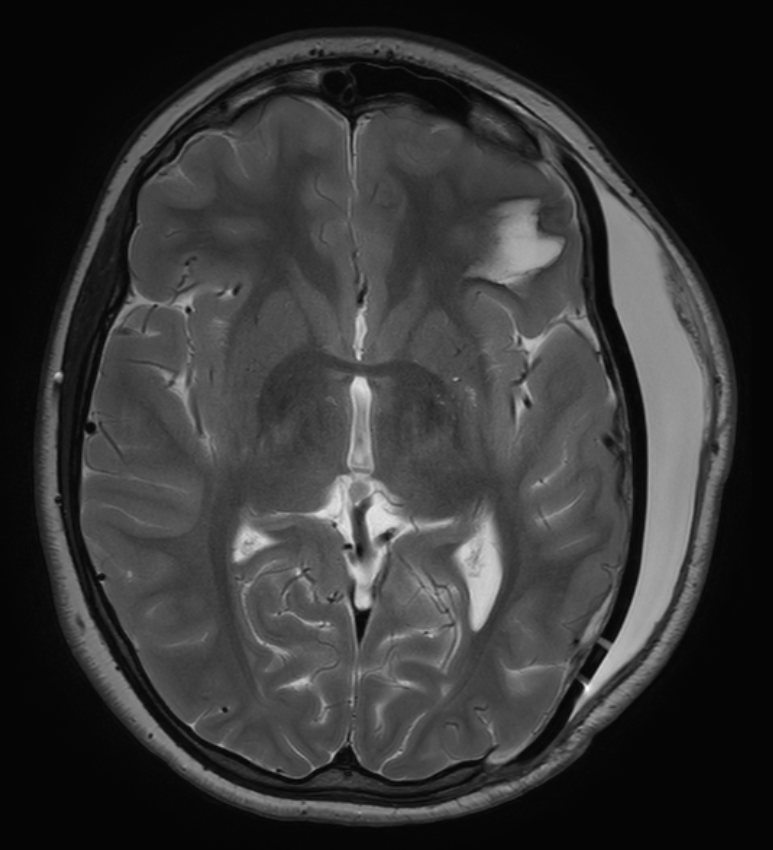

Bildgebung

Ein Liquorkissen kann durch die klinische Untersuchung diagnostiziert werden als auch in einer CT oder MRT Bildgebung dargestellt werden.